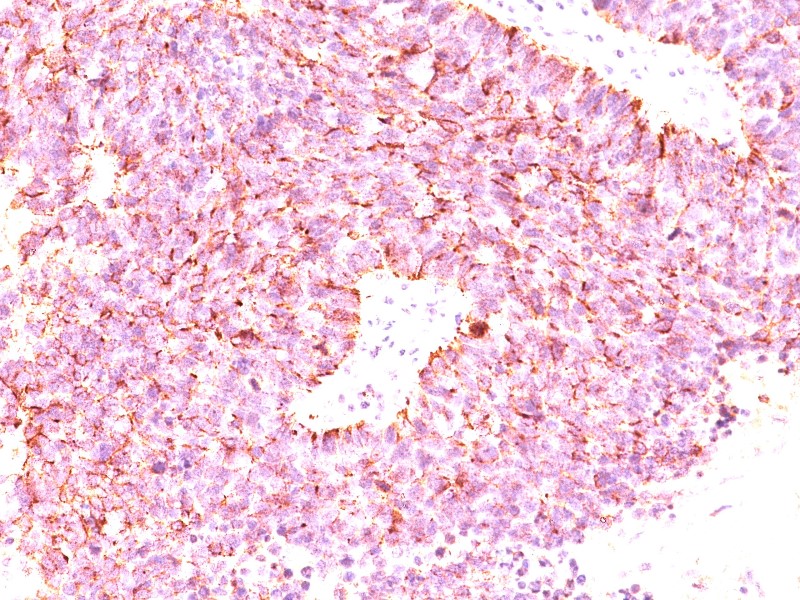

Οι όγκοι αυτοί ιστολογικά χαρακτηρίζονται από την παρουσία νευροεκκριτικών κοκκίων τα οποία δίνουν θετική τη χρώση χρωμογρανίνης Α, κάτι που αποτελεί και μέθοδο ιστολογικής ανίχνευσής τους. Οι χρωμογρανίνες είναι παρούσες σχεδόν σε όλους τους ενδοκρινείς ή νευρικούς ιστούς. Τα επίπεδα πλάσματος της χρωμογρανίνης Α (CgA) βρίσκονται υψηλά σε περισσότερο από το 90% των ασθενών με διάφορα pNETs, χωρίς τα επίπεδα αυτά να είναι σίγουρο ότι συμπεριφέρονται ως δείκτες κακοήθειας όπως είχε παλαιότερα λεχθεί. Το παγκρεατικό πολυπεπτίδιο (PP) έχει προταθεί επίσης για να διαδραματίσει αυτό το ρόλο, αλλά δεν χρησιμοποιείται λόγω της χαμηλής ευαισθησίας και ειδικότητας που έχει (54% και 57% αντίστοιχα) στα PNETs. Ο συνδυασμός και των δύο αυτών πεπτιδίων για τα pNETs και για τα NF-pNETs συγκριτικά με τη χρωμογρανίνη, δίνει ευαισθησία που ανέρχεται στο 95% έναντι 75%.